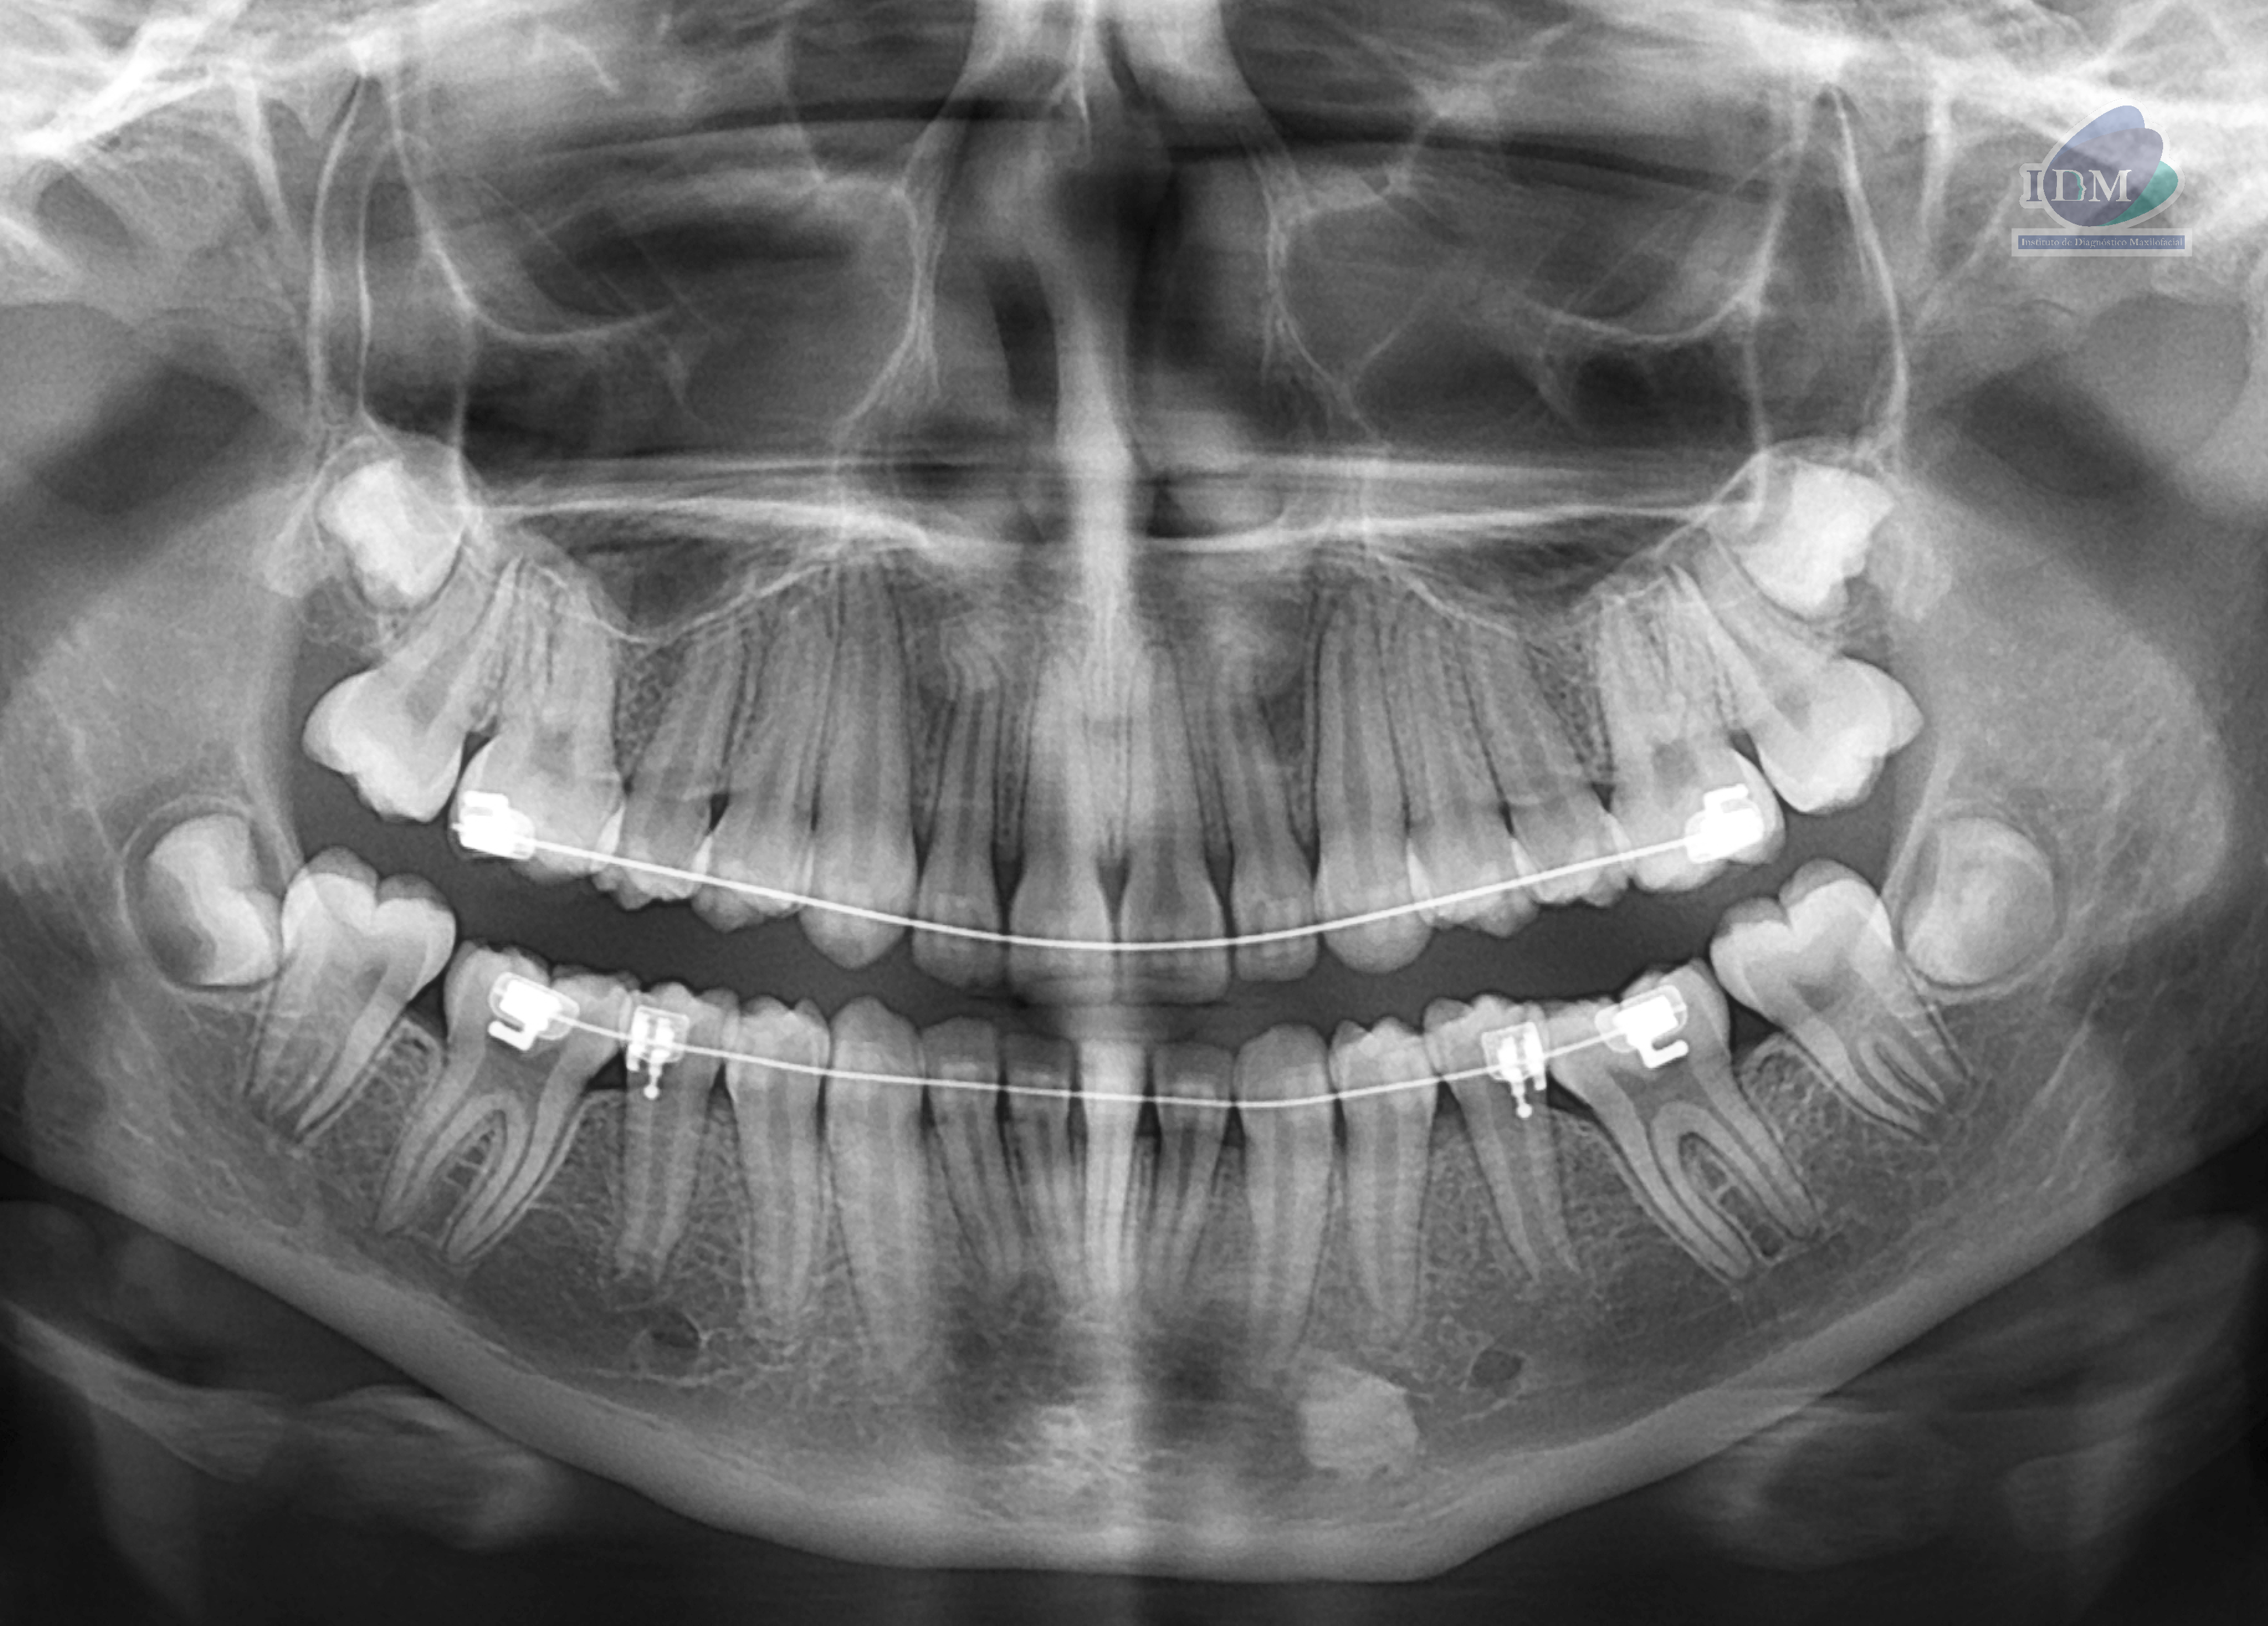

En la radiografía panorámica (Figura 1), se aprecia imagen radiopaca proyectada en cuerpo mandibular izquierdo, de limites definidos y forma irregular, que se extiende en sentido cefálico caudal desde nivel apical de pieza 33 hasta cortical superior del conducto dentario inferior.

Radiografia Panorámica